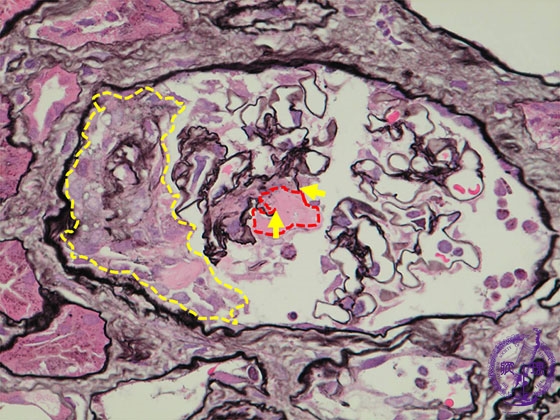

- ★(5)Crescent-forming glomerulonephritis

Microscopic findings ( PAM, high power view):ANCA-related glomerulonephritis. There is disruption of the glomerular loop basement membrane (yellow arrows) as well as fibrin exudates (red dotted line). Bowman’s space contains a cellular crescent (yellow dotted line).